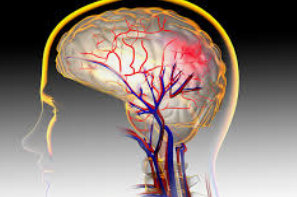

뇌동맥류는 뇌 속의 동맥 벽이 비정상적으로 확장되어 풍선처럼 부풀어 오른 상태를 말합니다. 이러한 현상은 혈관 벽이 약해져 혈압을 견디지 못하면서 발생하며, 조기 발견과 치료가 매우 중요합니다.

대부분의 뇌동맥류는 뇌 기저부에 위치한 윌리스환에서 발생합니다. 뇌동맥류의 크기는 수 밀리미터에서 수 센티미터까지 다양하며, 시간이 지나면서 점차 커질 수 있습니다. 크기가 커지면 주변 신경을 압박하여 다양한 증상을 유발할 수 있습니다.

뇌동맥류는 발견 즉시 적절한 치료가 필요합니다. 특히 파열될 경우 뇌지주막하출혈과 같은 생명을 위협하는 상황을 초래할 수 있습니다. 파열된 동맥류는 갑작스러운 극심한 두통과 함께 심각한 신경학적 증상을 동반할 수 있어 신속한 의료 개입이 필수적입니다.